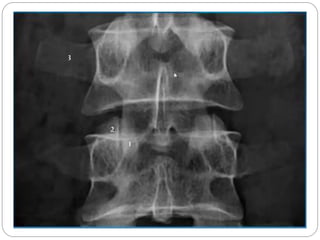

Vértebra lombar

Os corpos vertebrais são maiores, apresenta o forame vertebral em forma triangular e processos mamilares. Pode ser diferenciado também por não apresentar forame no processo transverso e nem a fóvea costal.

ASPECTOS GERAIS DA VERTEBRA LOMBAR

Os corpos vertebrais da região lombar possuem a forma de um rim.

Cada corpo vertebral possuem margens laterais côncavas e anteriores convexas

Sua dimensão transversa de cada um excede sua dimensão ântero-posterior

Vértebra lombar Oscorpos vertebrais são maiores, apresenta o forame vertebral em forma triangular e processos mamilares. Pode ser diferenciado também por não apresentar forame no processo transverso e nem a fóvea costal.

ASPECTOS GERAIS DAVERTEBRA LOMBAR Os corpos vertebrais da região lombar possuem a forma de um rim. Cada corpo vertebral possuem margens laterais côncavas e anteriores convexas Sua dimensão transversa de cada um excede sua dimensão ântero-posterior